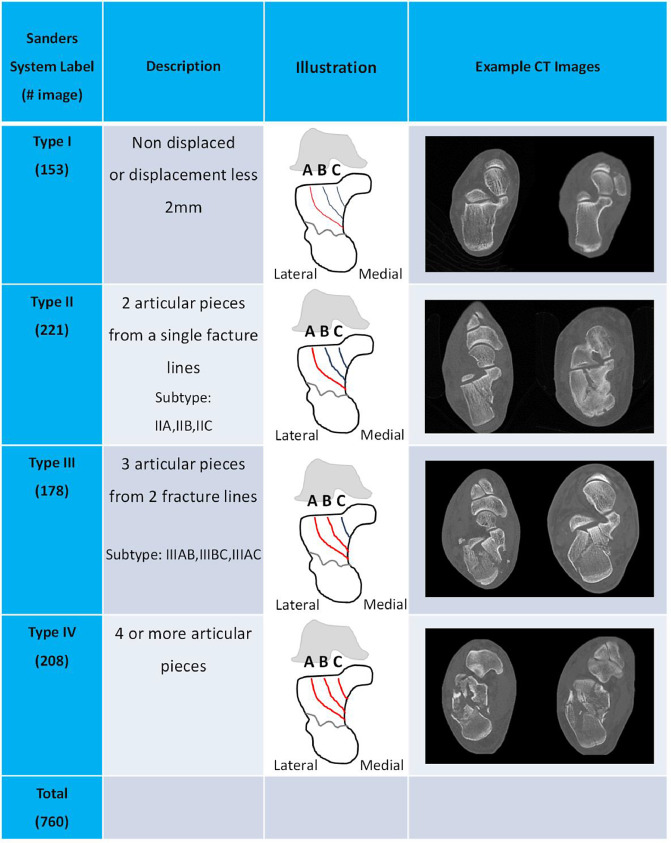

Calcaneus — Sanders Classification (CT-based)

The Sanders classification uses a coronal CT cut through the widest portion of the posterior facet of the subtalar joint. The location of primary fracture lines within the posterior facet determines type.

| Type | Description |

|---|---|

| I | Nondisplaced (regardless of number of fragments) |

| II | Two-part posterior facet — subdivided A, B, C from lateral to medial |

| III | Three-part — two fracture lines in the posterior facet |

| IV | Four or more fragments (comminuted) — primary subtalar arthrodesis often preferred |